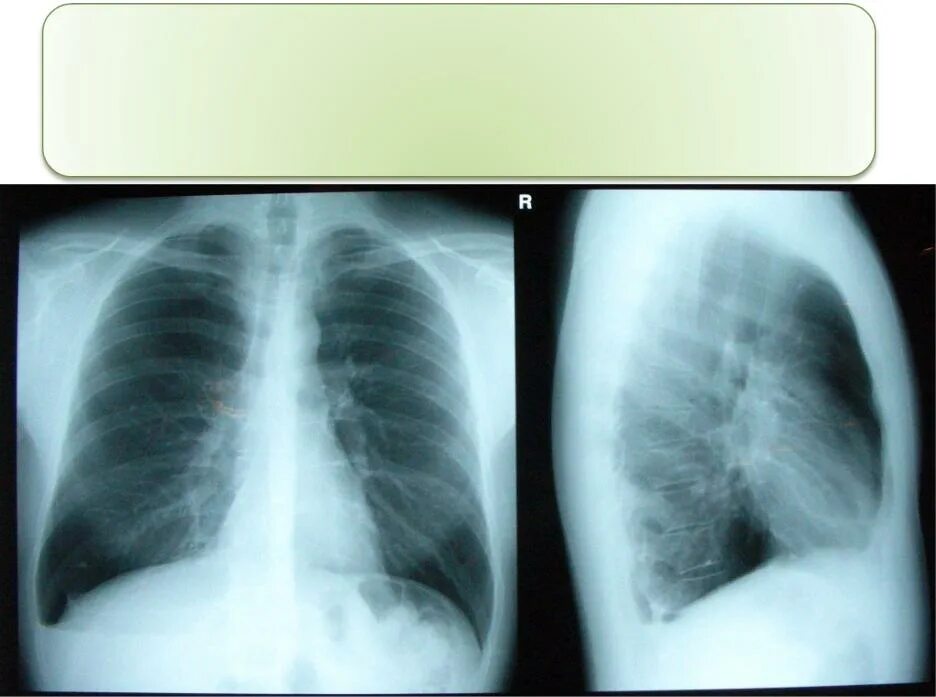

Флюорография видно ли курящего электронную сигарету